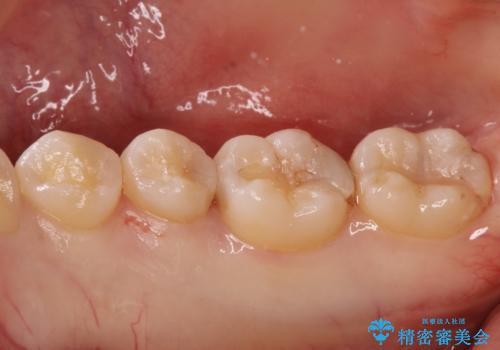

自然な見た目のセラミックインレー

セラミックインレーによる修復を行っております。

自然な見た目に満足して頂きました。

保険治療で使える材料には制限があり、見た目だけでなく精度でも劣ります。当院でのセラミックインレーは歯とのつなぎ目を拡大鏡で確認して精度高く仕上げるため、むし歯のリスクを限りなく少なくできるよう治療します。